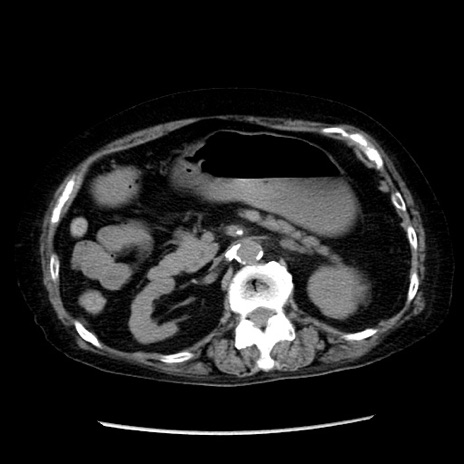

冠状断像

症例14(横断像)

【症例】 90歳代女性

【主訴】 腹痛・嘔吐

【現病歴】今朝から左側腹部痛を認めた。 経過観察していたが、嘔吐を認めたため来院。

【既往歴】 子宮癌術後

【身体所見】 意識清明、BP 127/54mmHg、P 98bpm Sp02 95%(RA)、BT 35.8°C、腹部平坦・軟腸ぜん動音聴取良好、右下腹部圧痛(+) 反跳痛なし

【データ】WBC 9800、CRP 0.46